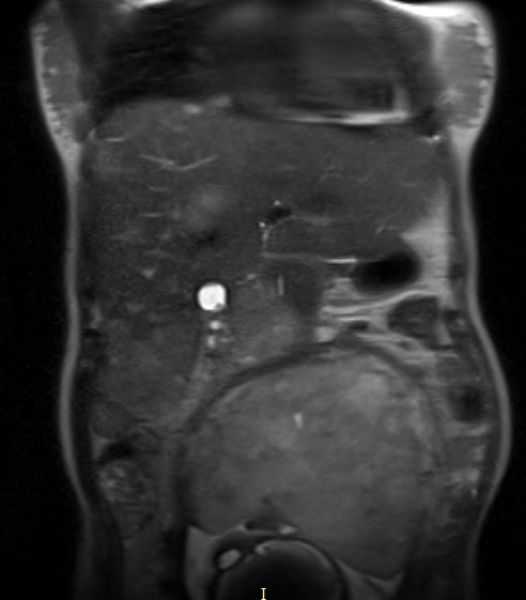

Заблуждения и факты о внутрибрюшной беременности